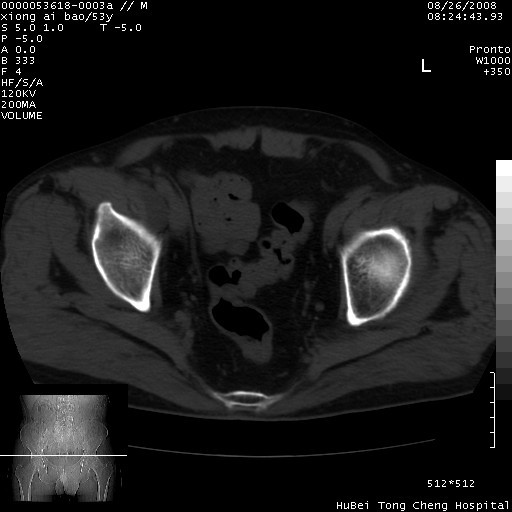

标题: CT15583:M,53Y。请老师指教分析骨盆及其他病变。 [打印本页]

标题: CT15583:M,53Y。请老师指教分析骨盆及其他病变。

双侧股骨头无菌坏死,左侧腹股沟斜疝。

非常典型病例,双侧股骨头坏死伴双髋关节周围软组织肿胀,左腹股沟疝。

双侧股骨头坏死伴双髋关节周围软组织肿胀,左腹股沟疝。